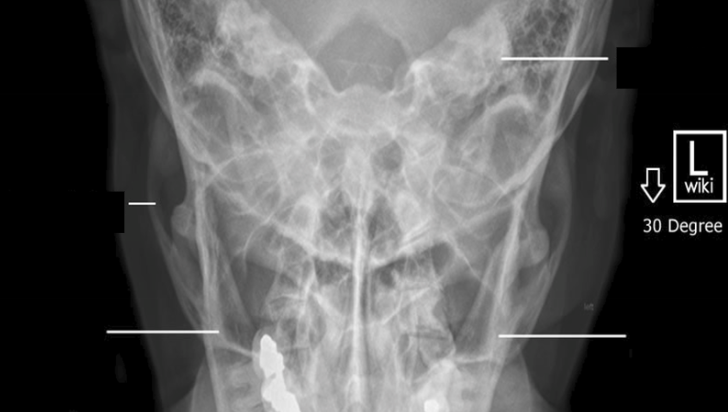

Please label